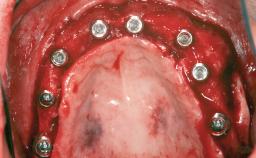

Staged bone augmentation of the alveolar ridge is indicated whenever a proposed implant site is deficient and will not support implant placement with simultaneous grafting. This is particularly true of healed sites presenting with facial flattening of the ridge. Since primary stability cannot possibly be achieved in this situation, it is recommended to use a staged approach with guided bone regeneration (GBR) for correct three-dimensional placement of the implant. In the anterior maxilla, staged GBR procedures are conducted not only to provide adequate bone volume for implant placement but also to restore a proper and stable contour of the orofacial ridge for improved long-term esthetics. A case is presented that demonstrates the technique for single-tooth replacement utilizing a staged approach with a particulate grafting material. A 50-year-old man whose tooth 11 was missing presented for consultation to the Center for Implant Dentistry in January 2010.

Bone Augmentation Horizontal|Staged

Augmentation Materials Allogenous|Membrane

Bone Volume Deficient horizontally, requiring prior grafting